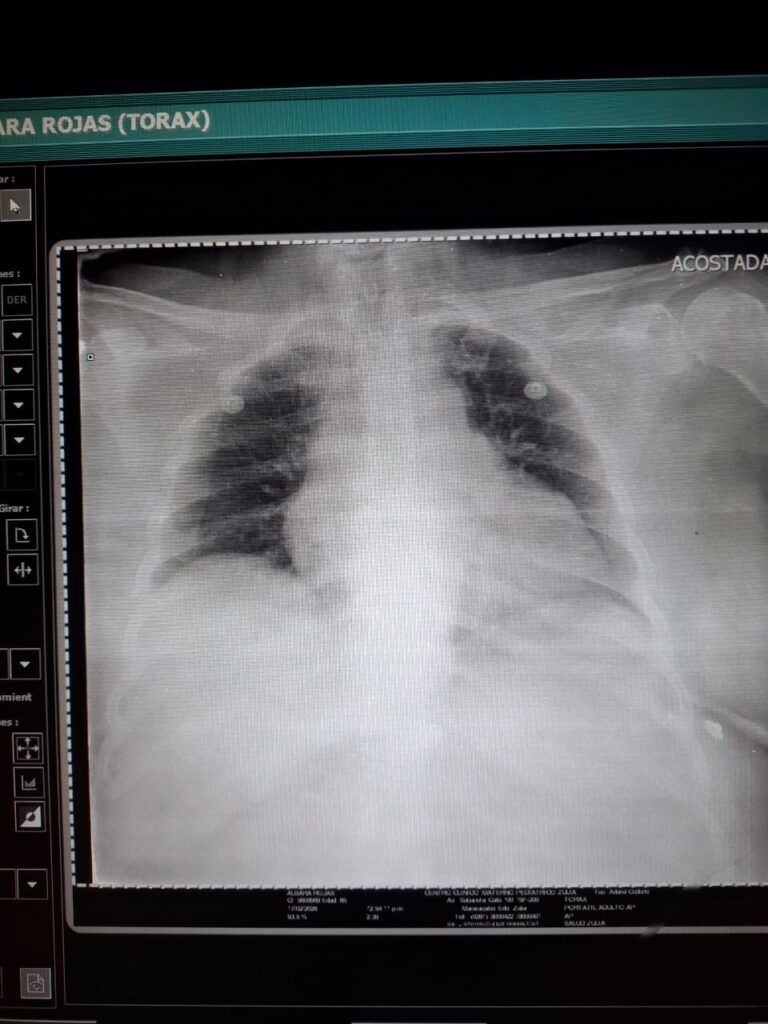

Albora Rojas, de 65 años, se enfrenta a un difícil momento de salud debido a una cardiopatía isquémica crónica, además de padecer hipertensión y diabetes, por lo que requiere ayuda de terceros para realizarse una angioplastia coronaria con la colocación de un stent.